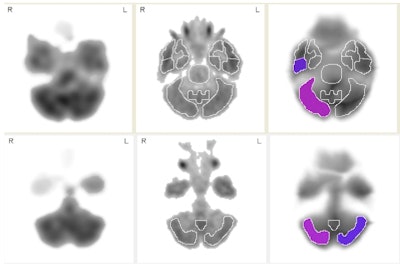

In the comparison of retired players to normal subjects, Raji and colleagues found significantly diminished regional cerebral blood flow in the right inferior lateral posterior temporal cortex and right cerebellum, and significantly elevated regional cerebral blood flow in the right posterior medial temporal cortex and right sensorimotor cortex. Defensive backs had lower blood flow compared to offensive linemen in the left superior frontal cortex.

The most striking finding was the abnormally low areas of blood flow in the right posterior temporal lobe of the retired football players compared to normal subjects, Raji said.

"The temporal lobe finding is especially important because that's the area that often shows early abnormality in dementias, such as frontal temporal dementia or Alzheimer's," he explained. "That is relevant to this study because, even though none of our players had these dementias, traumatic brain injury is a risk factor for dementia."